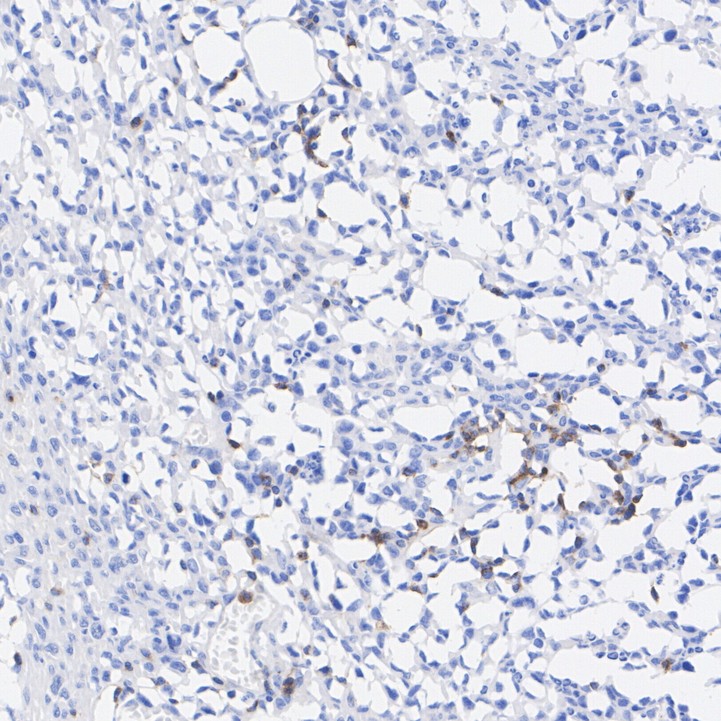

Immunohistochemical analysis of paraffin-embedded human spleen tissue with Rabbit anti-CD2 antibody (HA751033) at 1/200 dilution.

The section was pre-treated using heat mediated antigen retrieval with Tris-EDTA buffer (pH 9.0) for 20 minutes. The tissues were blocked in 1% BSA for 20 minutes at room temperature, washed with ddH2O and PBS, and then probed with the primary antibody (HA751033) at 1/200 dilution for 1 hour at room temperature. The detection was performed using an HRP conjugated compact polymer system. DAB was used as the chromogen. Tissues were counterstained with hematoxylin and mounted with DPX.